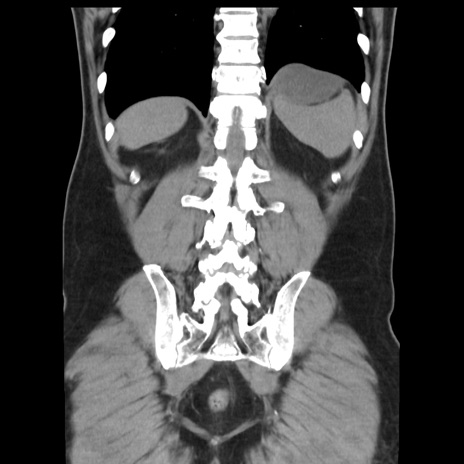

症例16(冠状断像)

【症例】 70歳代男性

【主訴】 腹痛、嘔吐

【現病歴】 約1ヶ月前より間欠的に腹痛と嘔吐あり、当院消化器内科を受診したところCTで多発する肝臓のLDAを指摘され、精査中であった。以降は消化器症状は安定していたが、2日前より嘔気と腹痛があり、同日より排便・排ガスが消失した。改善認めず、 本日、救急外来を受診した。

【身体所見】意識清明・会話良好、BT 36.3℃、BP 127/80mmHg、 P 80bpm、腹部:膨満あり、平坦・軟、上腹部正中および下腹部正中に圧痛あり、反跳痛なし、筋性防御なし。

【データ】WBC 7200、CRP 0.77